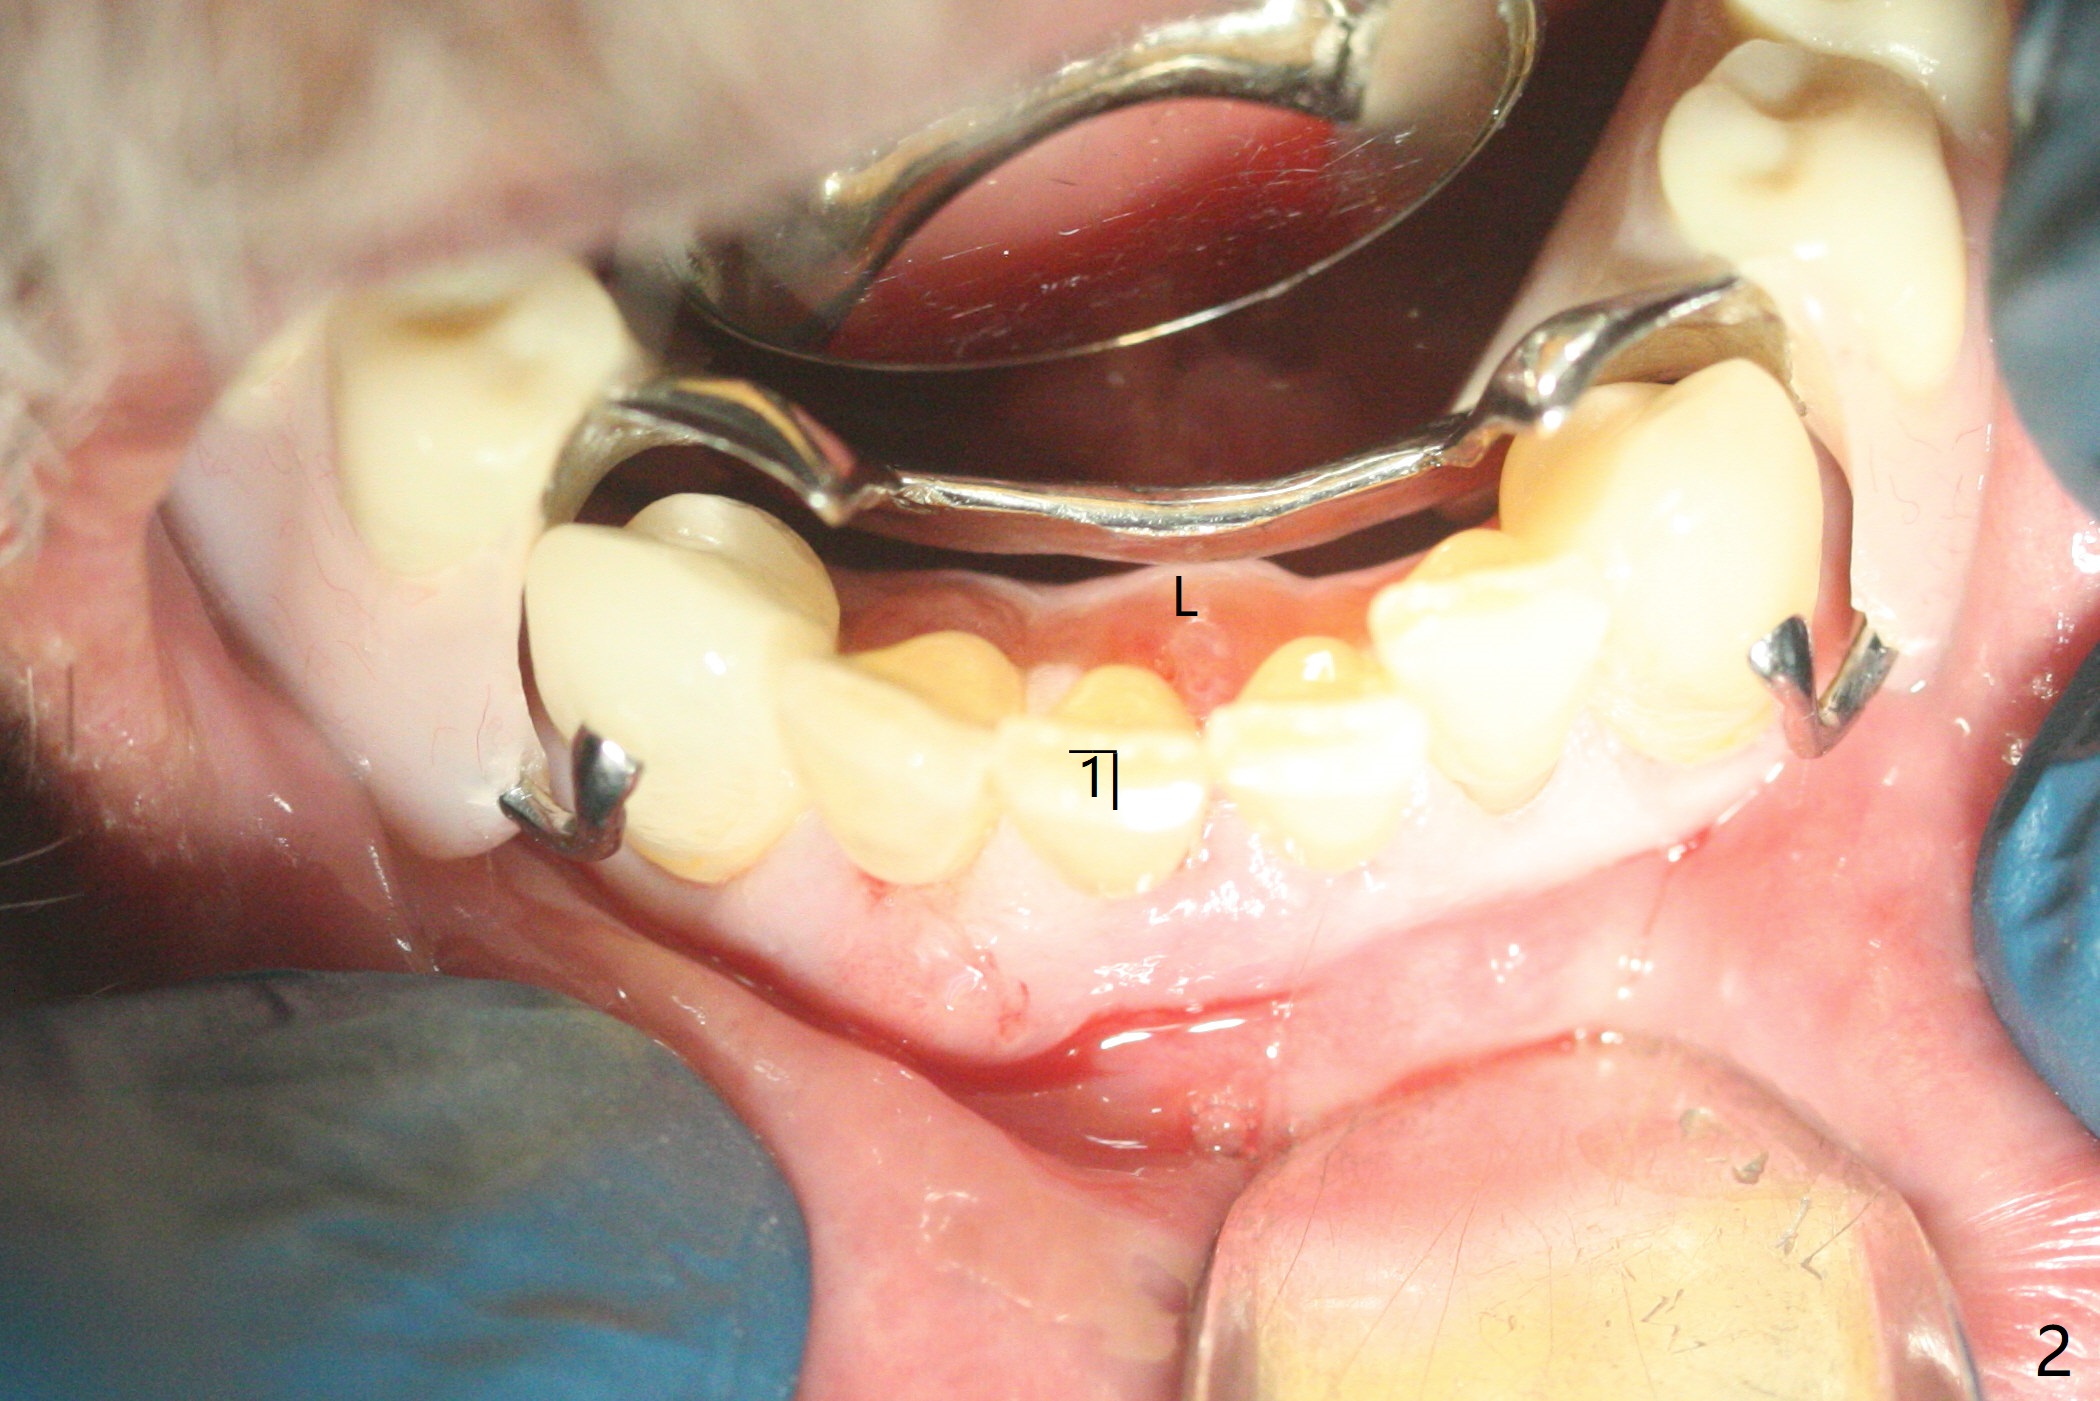

70岁男有上颌全口义齿,下颌局部义齿,后者由于右下切牙肿痛,松动无法戴入(图一至三),左下1骨质吸收严重,但是没有症状(图四)。理想治疗拔除右下1,2,即刻植牙,预防右下三断裂,不过病人没有思想准备,同意即刻植骨(图五,6个月吸收膜)。右下1舌侧,2颊侧脓肿(图一,二),拔牙时发现相应骨质缺损严重。四个月后在右下2植牙,做悬臂桥。当左下1不行时,做单个植牙,这样病人至少可以暂时使用局部托牙。